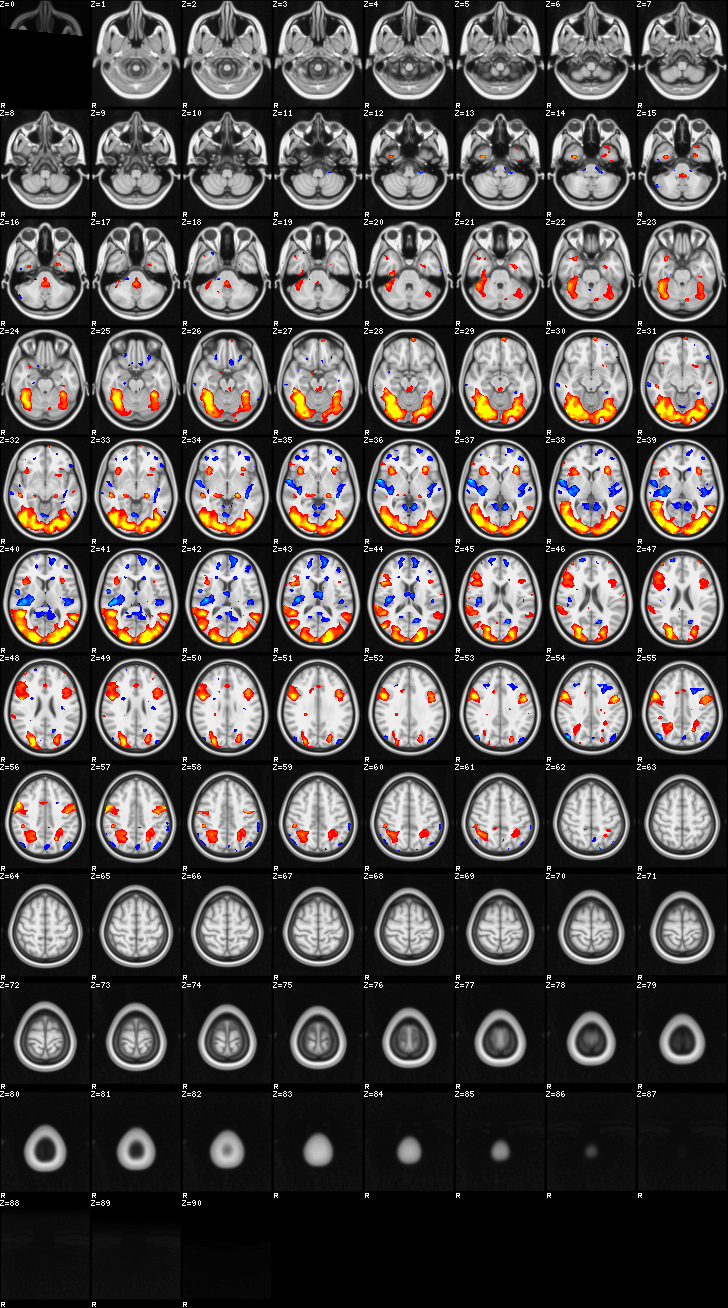

Mixed Effect (flame1)¶

ATM it is 8 subjects, 8 mm FWHM spatial smoothing, preliminary results only

Images thresholded abs value > 2.3 and colormap goes from 2.3 to 5 (red->yellow) or -2.3 to -5 (blue->lightblue)

- MOTOR

- Although based on the subject responses, since they occurred only during oddball, it reflects both oddball and motor reaction

02-MOTOR¶